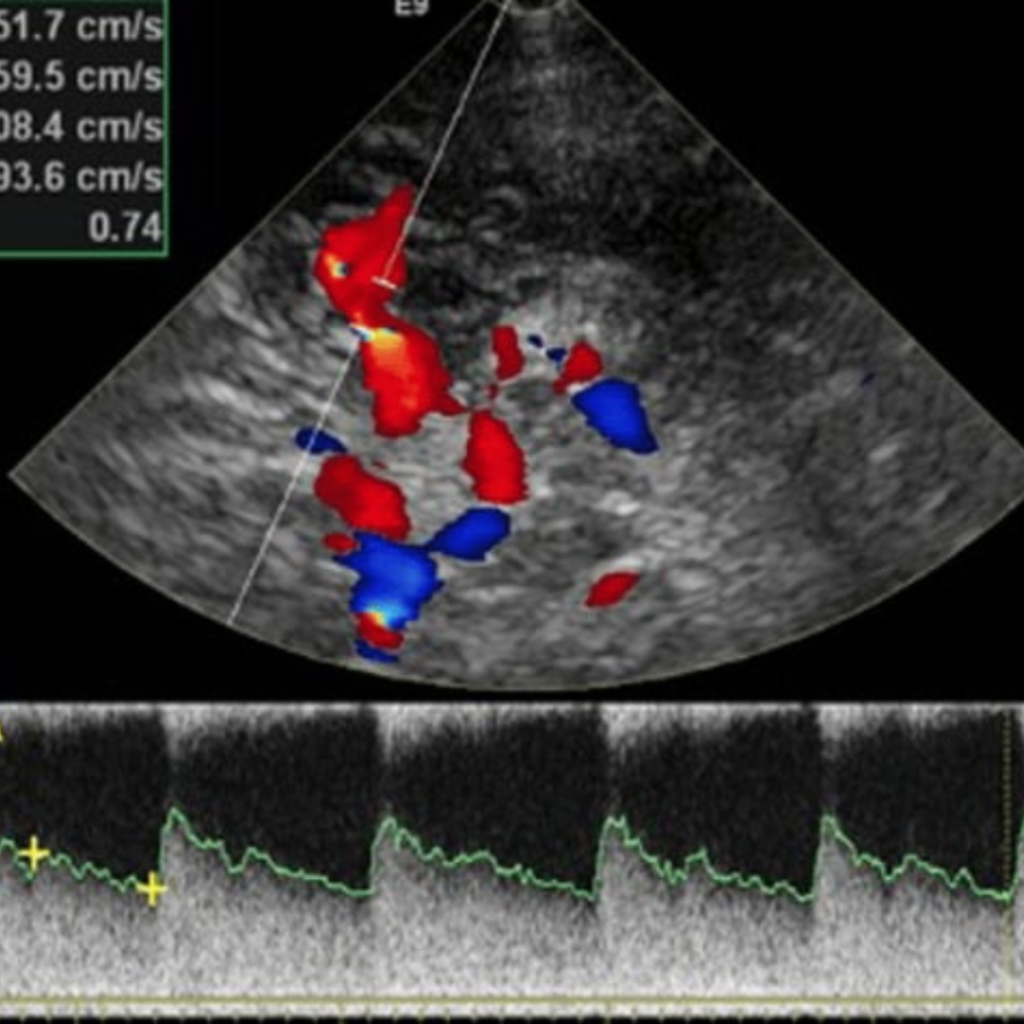

Уромед эмнэлгийн мэдрэлийн кабинет нь БНСУ-ын 2025 онд үйлдвэрлэсэн орчин үеийн шилдэг Samsung Medison V6 загварын хиймэл оюун ухаан дээр суурилсан аппаратаар тархины судасны өнгөт хэт авиан Допплер-Дуплекс шинжилгээг хийдэг.

тархины судасны өнгөт хэт авиан Допплер-Дуплекс шинжилгээгээр

Тархины судасны цусны урсгалын хурд, хөдлөл зүй

Хиймэл оюун ухаан дээр суурилсан автомат хэмжилтээр маш өндөр түвшинд нарийвчлан дүрслэн харж үүссэн судасны атеросклерозын товруу, эмгэгийг хэмжиж, судасны нарийслын хувийг тогтоож, бөглөрөл буй эсэхийг шууд харж оношлогоо хийдгээрээ маш давуу талтай.

Тархины судасны өнгөт хэт авиан дуплекссонографи шинжилгээ нь тархины судасны өвчнүүд, тархины цус хомсрох харвалт, шигдээс үүсэхээс урьдчилан сэргийлэх, эрт илрүүлэх, оношлоход чухал ач холбогдолтой дүрс оношилгооны бусад аргуудтай харьцуулахад харьцангуй өртөг багатай, цаг хугацаа хэмнэсэн инвазив бус шинжилгээний арга юм.